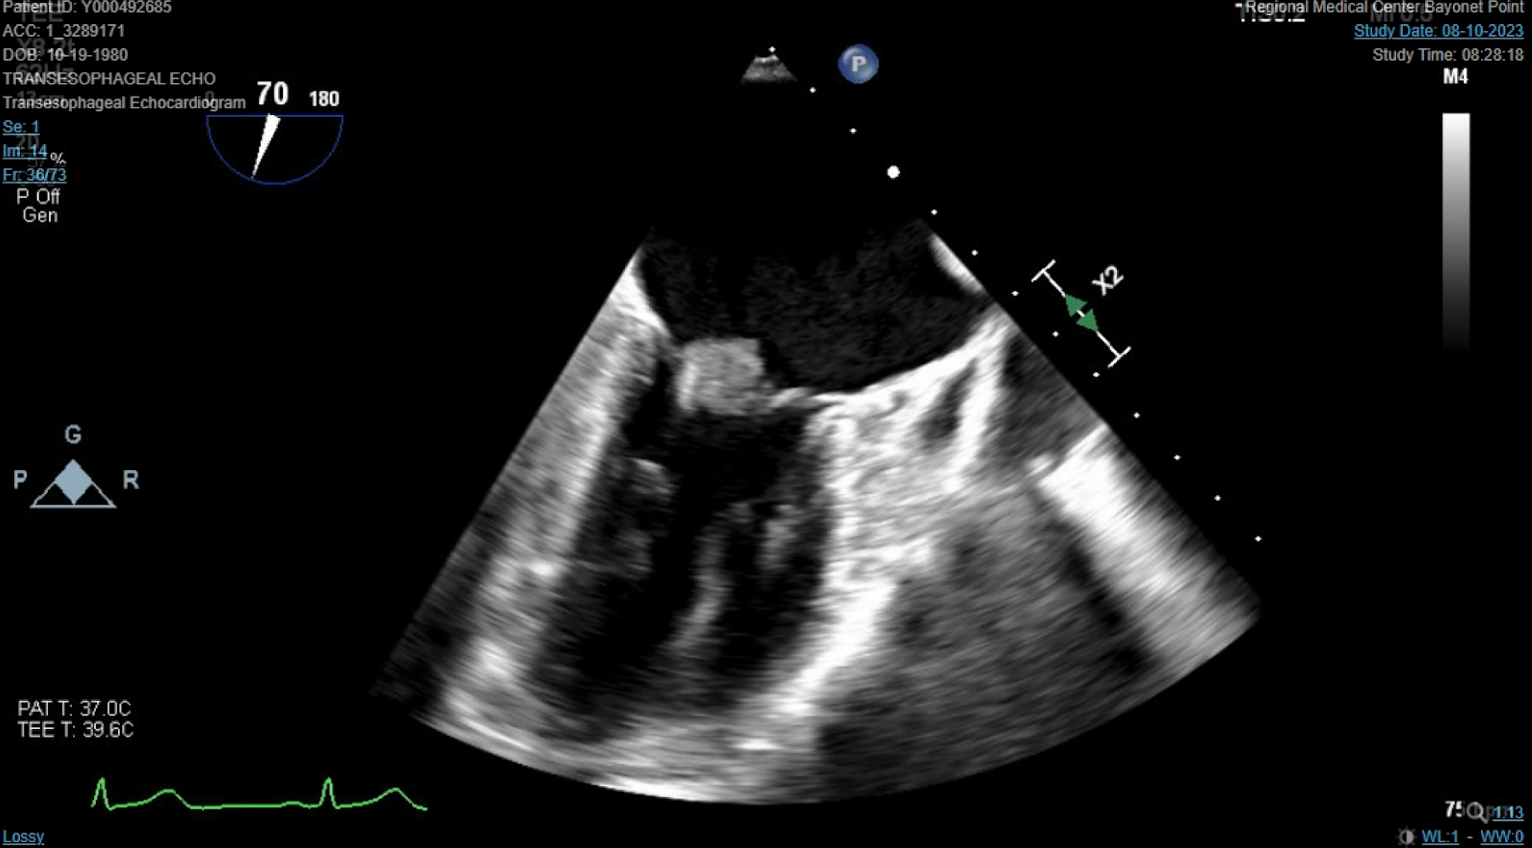

Abstract Body (Do not enter title and authors here): We describe a 42-year-old female with a past medical history significant for antiphospholipid syndrome (APS) who presented as a transfer to our facility for evaluation of stroke-like symptoms. She experienced acute onset dysarthria, left-sided weakness and a fixed rightward gaze preference. She was not a candidate for tenecteplase due to outpatient direct oral anticoagulant therapy. Computed tomography (CT) imaging of the head confirmed an acute infarct to the middle cerebral artery territory. She was taken for an emergent mechanical thrombectomy which she tolerated well. Repeat CT imaging ruled out hemorrhagic conversion. Transthoracic echocardiography revealed a 1.3 cm x 1.2 cm spherical mobile mass on the mitral valve, associated with a moderate to severe mitral regurgitation that was confirmed by transesophageal echocardiogram. The patient's respiratory status unfortunately declined and was consequently intubated. Blood cultures were negative and there was no history of intravenous drug use. The vegetation was considered marantic, representing nonbacterial thrombotic endocarditis (NBTE) secondary to APS and medication nonadherence. Cardiothoracic surgery offered surgical valve replacement after clinical recovery on an outpatient basis. She was subsequently extubated, transitioned to warfarin as recommended by hematology, weaned off supplemental oxygen, and discharged to inpatient rehab.